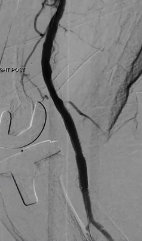

Mustapha CTO Crossing Retrograde Pedal Access

Video AMP 2021

07/22/2021

In this Live CLI case, endovascular intervention is performed via the brachial and pedal arteries in a patient with a complex CFA and SFA CTO with limited access options. Multiple crossing and treatment modalities are utilized in this case to...